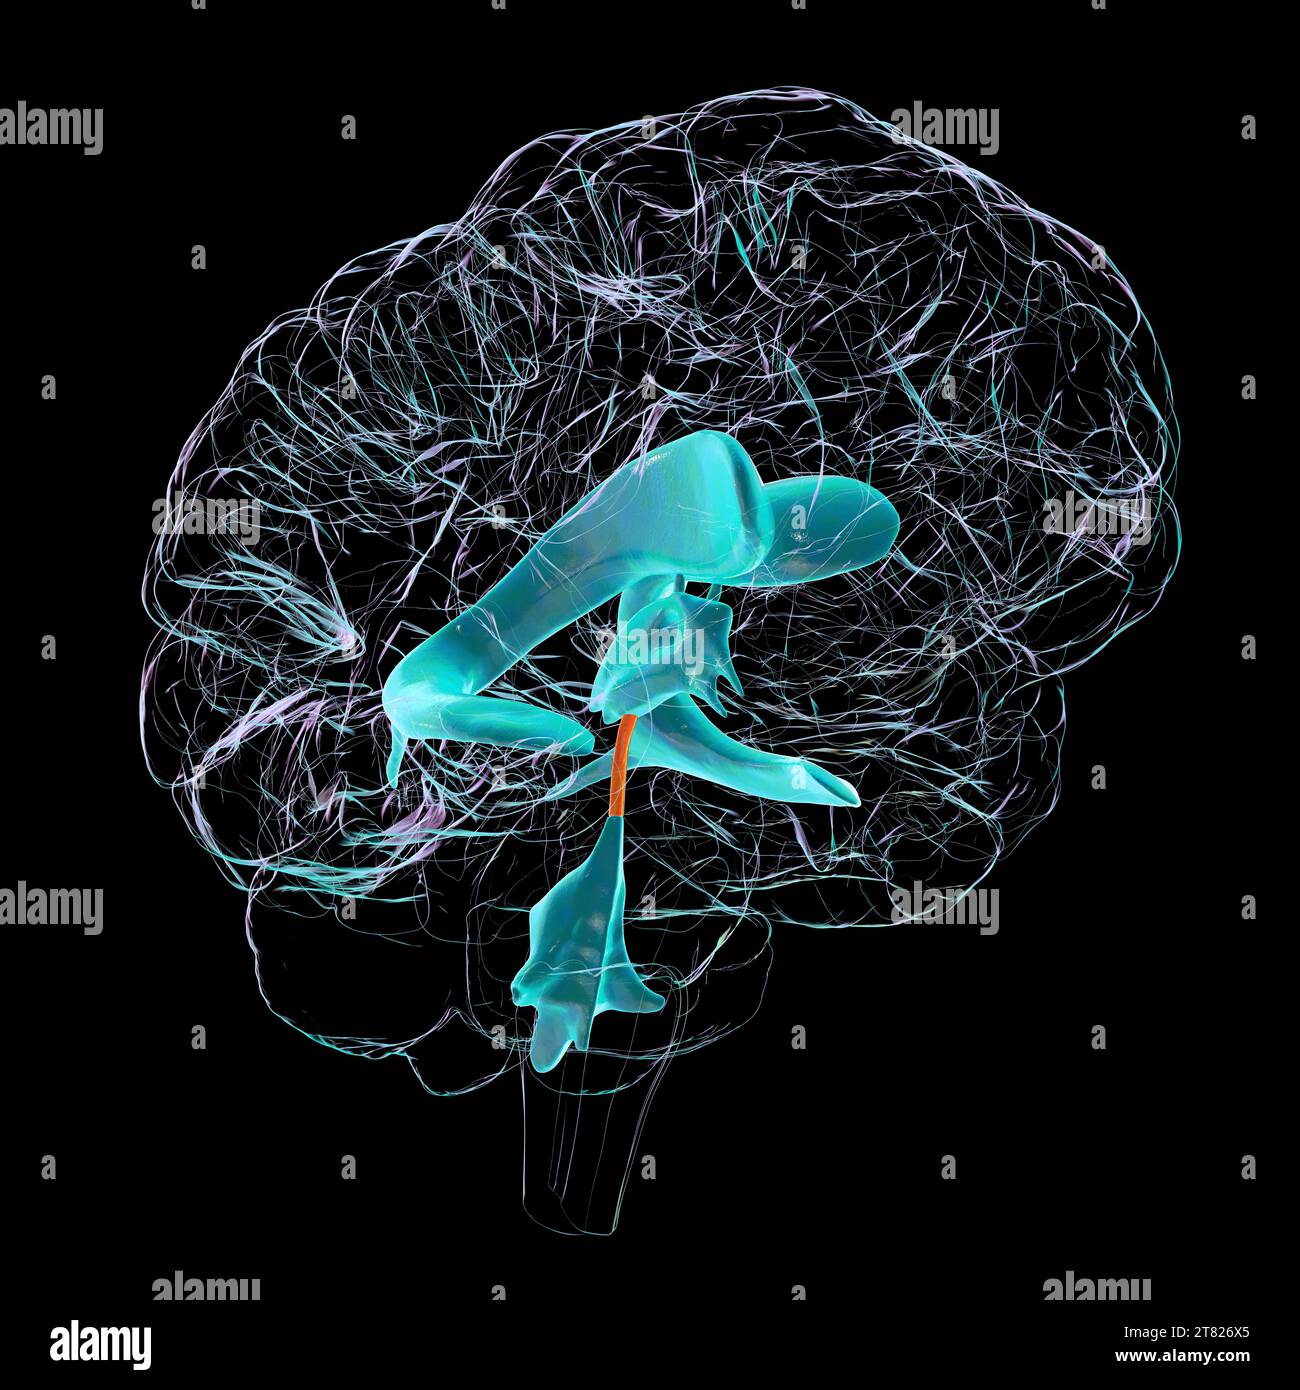

RF2T7NGWH–Ventrikel und zerebrales Aquädukt laterale Röntgenansicht 3D-Rendering-Illustration. Menschliches Gehirn und Ventrikelsystem Anatomie, Medizin, Gesundheitswesen, Scienc

RF2T7NGWK–Ventrikel und zerebraler Aquädukt lateral in Farben Röntgenbild-3D-Rendering-Illustration. Menschliches Gehirn und Ventrikelsystem Anatomie, medizinisch, gesund

RF2T7NGWR–Ventrikel und Hirn-Aquädukt-Röntgenprofil Nahansicht 3D-Rendering-Illustration mit Körperkonturen. Anatomie des menschlichen Gehirns und des Ventrikelsystems,

RF2T7NGWW–Ventrikel und zerebraler Aquädukt in Farben Röntgenprofil Nahansicht 3D-Rendering-Illustration. Anatomie des menschlichen Gehirns und des Ventrikelsystems, medizinisch,

RF2T6AR96–Röntgenprofil des Gehirns oder sylvius aquädukt Nahansicht 3D-Rendering-Illustration mit Körperkonturen. Anatomie des menschlichen Gehirns und des Ventrikelsystems, med

RF2YX6R0N–Computerdarstellung des menschlichen Gehirns mit orangefarbenem Aquädukt und grünem Ventrikelsystem, die den Liquorfluss (CSF) zeigen.

RF2YX6R0K–Computerdarstellung des menschlichen Gehirns mit orangefarbenem Aquädukt und grünem Ventrikelsystem, die den Liquorfluss (CSF) zeigen.

RF2YX6R02–Computerdarstellung des menschlichen Gehirns mit orangefarbenem Aquädukt und grünem Ventrikelsystem, die den Liquorfluss (CSF) zeigen.

RF2YX6R05–Computerdarstellung des menschlichen Gehirns mit orangefarbenem Aquädukt und grünem Ventrikelsystem, die den Liquorfluss (CSF) zeigen.

RF2YX6R0G–Computerdarstellung des menschlichen Gehirns mit orangefarbenem Aquädukt und grünem Ventrikelsystem, die den Liquorfluss (CSF) zeigen.